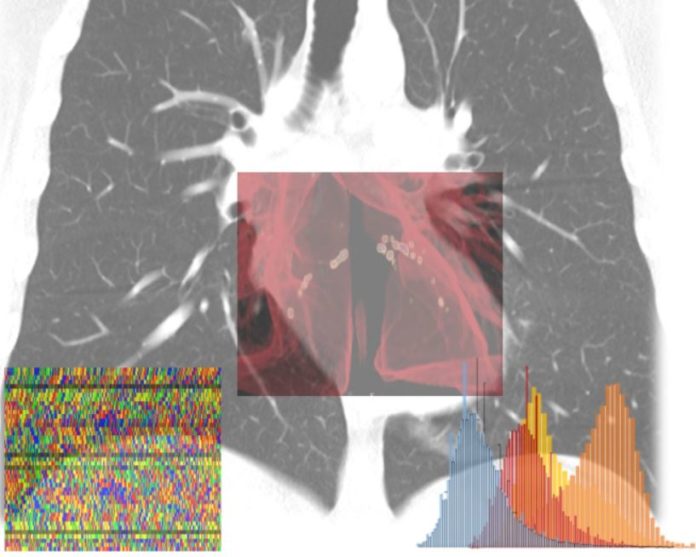

“L’Intelligenza Artificiale (IA) sta aiutando a combattere la pandemia in molteplici casi d’uso. Le piattaforme IA di calcolo accelerato e il software di NVIDIA sono sfruttate in tutto il mondo per aiutare a sequenziare e analizzare i genomi virali e dei pazienti, monitorare la diffusione delle infezioni e l’andamento della mobilità, accelerare lo sviluppo di nuovi farmaci e classificare e segmentare le immagini diagnostiche. Il progetto dell’ospedale San Raffaele stabilisce un nuovo punto di riferimento di qualità in termini di medicina personalizzata e NVIDIA è entusiasta di far parte di questa collaborazione”, afferma Francesco Torricelli, NVIDIA Country Director Italia & Iberia.